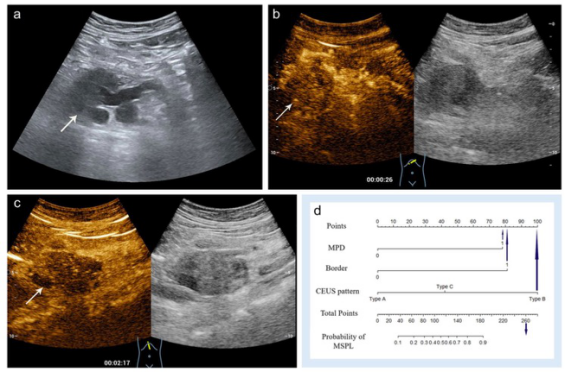

圖 一位60歲的女性,胰頭處有一個(gè)直徑為5.3厘米的低回聲實(shí)性病變。a 病變顯示邊界不清(箭頭)、主胰管擴(kuò)張(9毫米)。 b, c 動(dòng)脈期(b)和靜脈期(c)均顯示腫瘤低強(qiáng)化。病理顯示為分化不良的胰腺導(dǎo)管腺癌

本研究表明,在CEUS上,在AP和VP上表現(xiàn)為低強(qiáng)化、高或等強(qiáng)化或廓清、邊界不清以及MPD擴(kuò)張是MSPLs的獨(dú)立風(fēng)險(xiǎn)因素,因此本研究提出的基于這些預(yù)測因素構(gòu)建的列線圖可作為診斷MSPLs的一個(gè)有效影像學(xué)工具為臨床提供服務(wù)。

共有155名患者(平均年齡55±14.6歲,男/女=84/71)和78名患者(平均年齡59±13.4歲,男/女=36/42)分別被納入訓(xùn)練和驗(yàn)證組。在訓(xùn)練組中,強(qiáng)化前超聲中邊界不清和擴(kuò)張的主胰管、CEUS動(dòng)脈和靜脈期的低增強(qiáng)模式以及明顯增強(qiáng)后的廓清都與MSPLs獨(dú)立相關(guān)。用上述變量建立的預(yù)測列線圖模型在區(qū)分MSPLs和BSPLs方面表現(xiàn)良好,訓(xùn)練集的曲線下面積(AUC)為0.938,驗(yàn)證集為0.906。